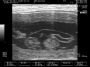

היום נעשתה בנוסף גם סריקה של האשכים ובלוטת הפרוסטטה של סילבר שלוקח גם הוא כמו מארם חלק במחקר הקשור ללימודי (רפואה וטרינרית) בנושא הריון והמלטה בכלבות. שני האשכים של סילבר הראו גדלים תואמים ואחידות בריקמה – דבר שנצביע על בריאות מושלמת מבחינה מינית. לרוב בכלבים בגיל הזה (5 שנים) כבר מתחילות ציסטות קטנות שאומנם אינן מסוכנות בשלב הזה אך מחייבות מעקב צמוד. בפרוסטטה של סילבר היתה מעט גדולה מה"נורמה" אך הדבר סביר בהחלט בהתחשב בפעילות המוגברת שהיתה לו לפני כחודש (בהרבעה הרצופה 5 ימים) ובעוד כחצי שנה יעבור סריקה נוספת כדי לעקוב אחרי המצב ולוודא שהבלוטה פועלת כראוי. בעיות פרוסטטה קיימות בכל הכלבים שאינם מסורסים (ללא יוצאים מן הכלל) ותלוייה בעיקר בגיל וברמת הפעילות המינית שהכלב מבצע – גיל מבוגר ופעילות מוגברת מעלים את הסיכון.